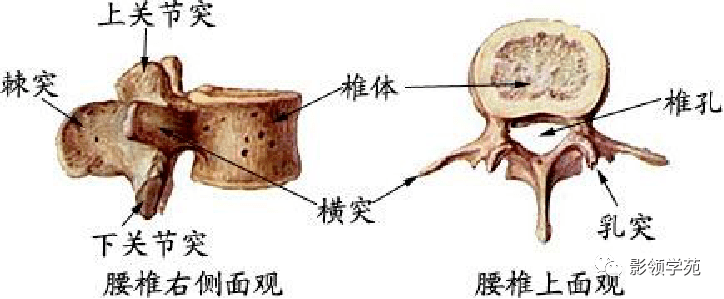

骨骼系统

骨骼系统